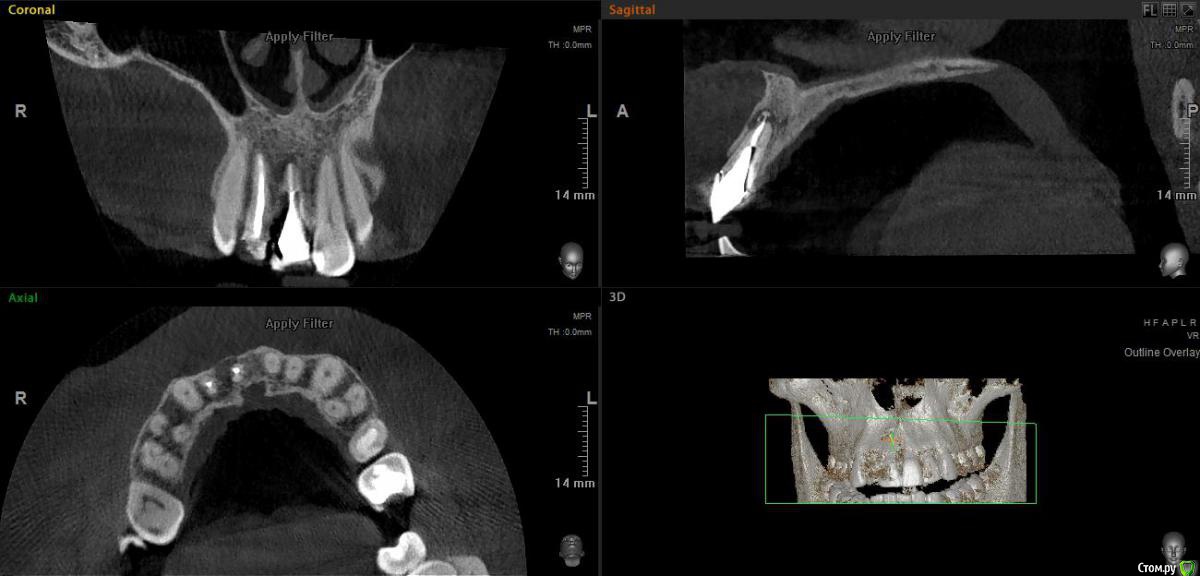

elen_only Опубликовано 14 июня, 2019 Поделиться Опубликовано 14 июня, 2019 Ретроградная пломбировка, резекция верхушки корня Ссылка на комментарий

elen_only Опубликовано 14 июня, 2019 Автор Поделиться Опубликовано 14 июня, 2019 (изменено) Доброго дня,коллеги! Ситуация такая: прислал ортопед пациента на резекцию верхушки корня. Пациент со всеми рисками ознакомлен,со всем согласен. Процедуру данную ранее не выполняла,т.к. не было необходимости. По хирургии все понятно,интересует ретроградная пломбировка. Специализированных ультразвуковых насадок нет. Можно ли обойтись без ретроградной пломбировки или сделать ее без УЗ насадок? Изменено 14 июня, 2019 пользователем elen_only Ссылка на комментарий

Дмитрий Л. Опубликовано 14 июня, 2019 Поделиться Опубликовано 14 июня, 2019 Корень резецируйте под скосом, затем ложбинку создайте шариком и пломбируйте. Без пломбировки смысла нет, так как ортоградно не будут перелечивать, на сколько я понял. Ну и УЗ насадка не такая и дорогая.Вы чем пломбировать-то думаете? Ссылка на комментарий

АнтонТЛТ Опубликовано 14 июня, 2019 Поделиться Опубликовано 14 июня, 2019 Можно обычную тонкую насадку загнуть.Сухость поля обеспечивается анестезией 1:50.000, либо ватные шарики смоченные в адреналине.Резецировать только под прямым углом к оси зуба, никаких под скосом. 1 Ссылка на комментарий

TiAn Опубликовано 14 июня, 2019 Поделиться Опубликовано 14 июня, 2019 Без насадки будет тяжело. Насадкой с алмазом можно и поверхность корня со всех сторон обработать.Пломбировка нужна, иначе все впустую. Лучше резецировать с минимальным скосом корня. И главное залезть внутрь канала пробкой на 2мм, а лучше больше. И стенки канала точно очистить от старого материала, без спецнасадки это очень тяжело сделать. 1 Ссылка на комментарий

elen_only Опубликовано 14 июня, 2019 Автор Поделиться Опубликовано 14 июня, 2019 Думаю пломбировать IRM или МТА Ссылка на комментарий